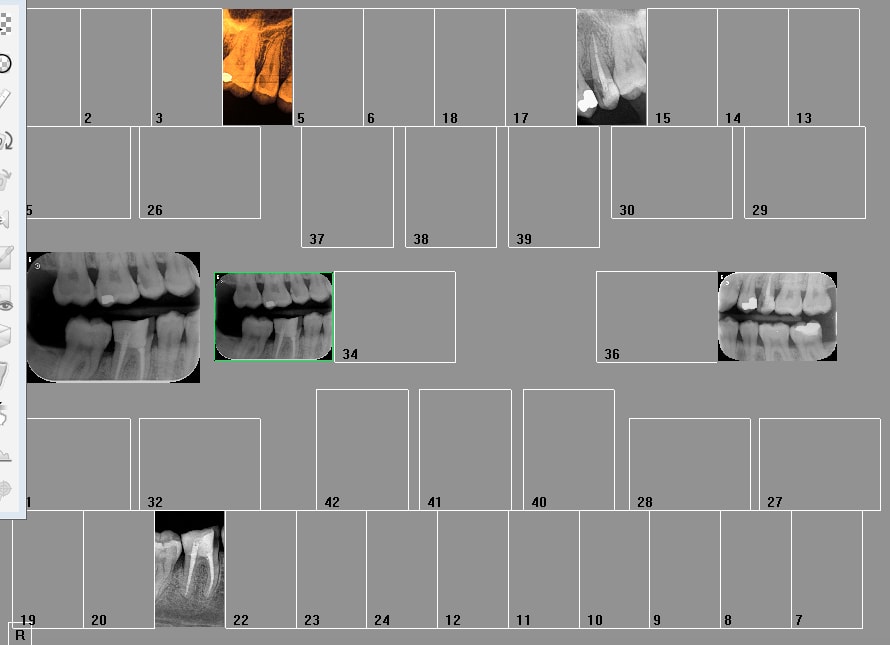

Pourquoi opposer les 2 systèmes ? Hein ? Je n'utilise les plaques que pour les rétro coronaires ( faut un capteur taille 2), je n'ai que 2 taille 1) . Pour le reste capteur. Et pour la définition capteur supérieur un seul temps d'exposition 0,09 s pour les plaques c'est à géométrie variable Jusqu'à 0,39 s par cliché. De plus une protection par cliché ca c'est vraiment la merde.

Comme ca ? 4 développements ca suffit pour les rétro coronaires. je me vois mal en faire 24 pour les 2 arcades complètes. -)